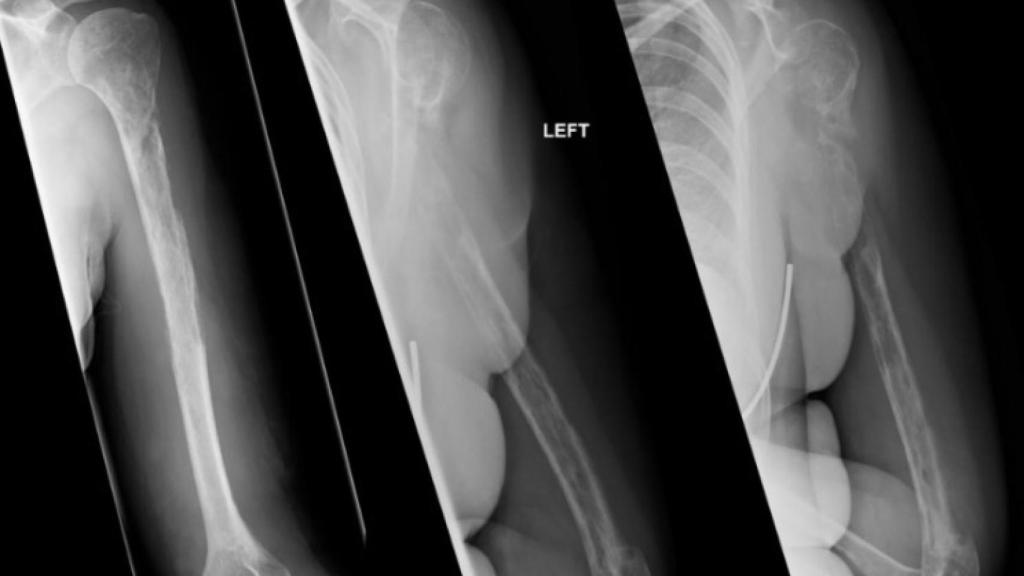

Radiografías consecutivas de la mujer.

Radiografías consecutivas de la mujer. BMJ Case Reports.

Las primeras pruebas parecían apuntar a un tumor, pero la biopsia descartaba esta posibilidad, por lo que el origen de su padecimiento parecía todo un misterio. Fueron necesarios 18 meses y varias fracturas óseas para que una nueva radiografía desvelara la peculiar realidad: sus huesos estaban desapareciendo.

La paciente sufría la enfermedad de Gorham-Stout, o síndrome del hueso fantasma, una rara patología que se caracteriza por un deterioro progresivo de los huesos, paralelo a la proliferación y dilatación de los vasos linfáticos.

Aunque puede darse en cualquier pieza ósea, el hueso que más a menudo se ve afectado por esta enfermedad es el húmero -en ocho de los 64 casos-, como en el caso de la paciente escocesa, que han relatado sus médicos en la revista BMJ Case Reports.